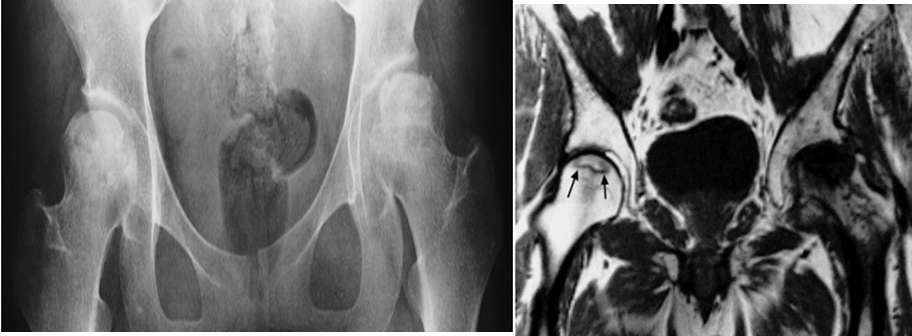

• MRI has now become the imaging modality of choice for demonstrating avascular necrosis A- Avascular necrosis. There is fragmentation with some sclerosis of both femoral heads

B- Coronal MRI scan showing avascular necrosis of both femoral heads. The changes on the left are very severe and advanced. The changes in the right hip are relatively early and show a rim of low signal demarcating the ischemic area (arrows)